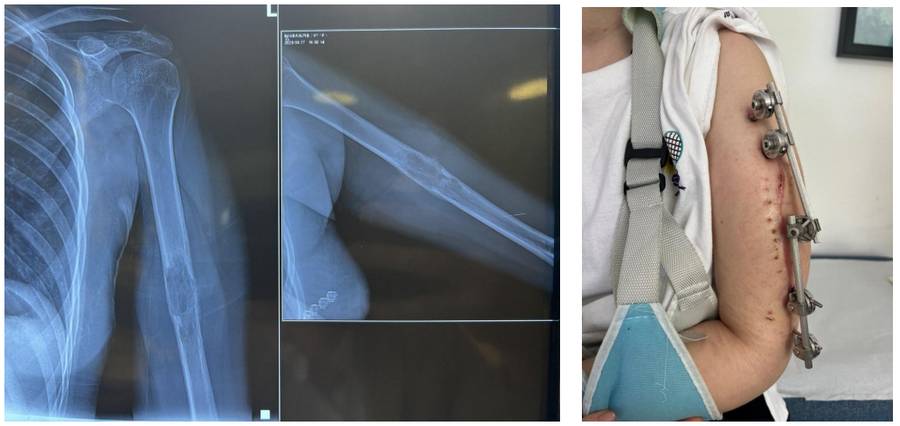

Ameliyat Öncesi: Röntgende humerus orta bölgede kemik harabiyetine neden olan düzensiz kitle ve uygulanan eksternal fiksatör görülmekte